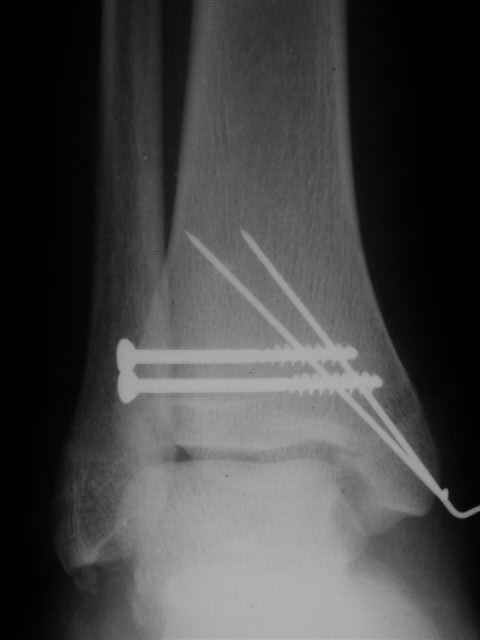

Я предупреждал, что ничего сверхъестественного. Каюсь, что одна из спиц прошла несколько дальше, чем нужно было, но главное - перелом стабилизирован и больной работает суставом в полном объёме, несмотря на представленную раннее травму коленного сустава.

Всего вам Доброго,

Евгений И Чекашкин